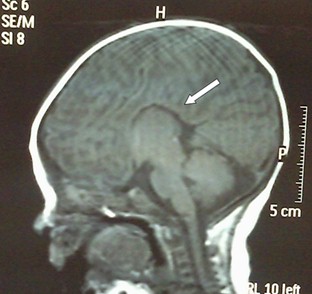

Figura 3. Caso 3: Agenesia completa del cuerpo calloso. Técnica RM, proyección sagital medial cerebral con secuencia de pulso SE-T1. Ausencia del cuerpo calloso (flecha banca) y comisura anterior.

CASO 3: Niño de 48 meses diagnosticado de parálisis cerebral infantil (PCI), síndrome malformativo, agenesia del cuerpo calloso (ACC) completa, cardiopatía, epilepsia parcial sintomática (en tratamiento con valproato sódico) y retraso en el lenguaje. De la exploración clínica se destacan dificultades para mantener la atención e inquietud. Obtiene un CD<70. En resonancia magnética (RM) se observa agenesia del cuerpo calloso (ACC) completa, dilatación de los ventrículos laterales a nivel occipital y temporal y ausencia de la comisura anterior o rostral (CA) (Figura 3). El paciente ha recibido tratamiento de atención temprana y se encuentra actualmente escolarizado.